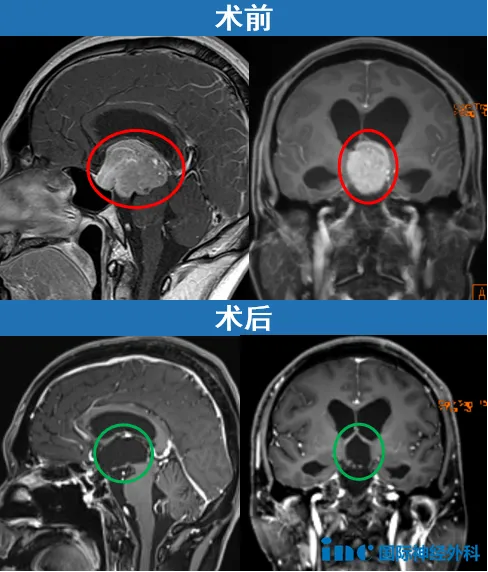

一例安全经鼻切除的巨大垂体瘤

35岁的江先生是因为头痛查出的垂体瘤,除了头痛,疲惫、食欲及注意力下降,甚至还出现了行走不稳的情况。这些症状对于一个30出头的青壮年,并不正常。就医检查发现鞍区及鞍上的巨大垂体瘤引发阻塞性脑积水,垂体瘤早已压迫到脑干、第三脑室及中央导水管,手术操作必须慎之又慎,哪怕不小心碰到任何一条神经,给他带来的可能都是终生的影响。

从找到INC福洛里希教授到远赴北京天坛医院成功手术,前后仅用了半个多月的时间。没有开颅,福洛里希教授最终通过经鼻内镜手术成功“挖”除了这个巨大的垂体瘤,术后恢复良好。“这是一次十分具有挑战性的手术,我很高兴为你成功手术!”